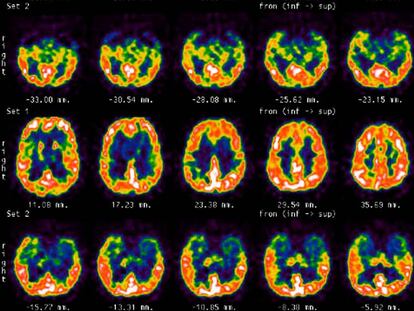

El placer del arte para nuestro cerebro

La ciencia investiga la base y el sentido biológico de la experiencia artística, más allá de los beneficios reconocidos